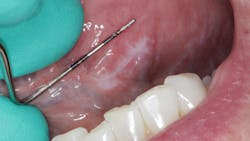

Patient: 62-year-old female

- 9 mm x 3 mm white leukoplakic patch of tissue on left ventral surface of the tongue

- Patient was unaware of its presence

- Not tender to palpation and could not be scraped off

- Noncontributory health history (patient was taking vitamin D supplements)